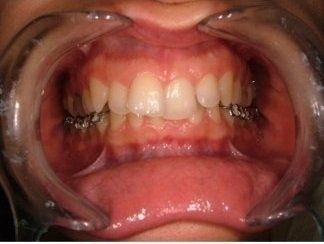

L'idea innovativa di applicare delle maniglie (brackets) sul lato interno dei denti, rivolto alla lingua anziché sul lato esterno rivolto al labbro ed esposto al sorriso, ha fatto sì che questa tecnica venisse denominata “linguale".

I risultati dell’ortodonzia linguale sono gli stessi di quelli ottenuti con gli apparecchi tradizionali, ma a causa della maggiore difficoltà che possono incontrare gli operatori questa tecnica è ancora usata solo da pochi specialisti in Italia e nel mondo.